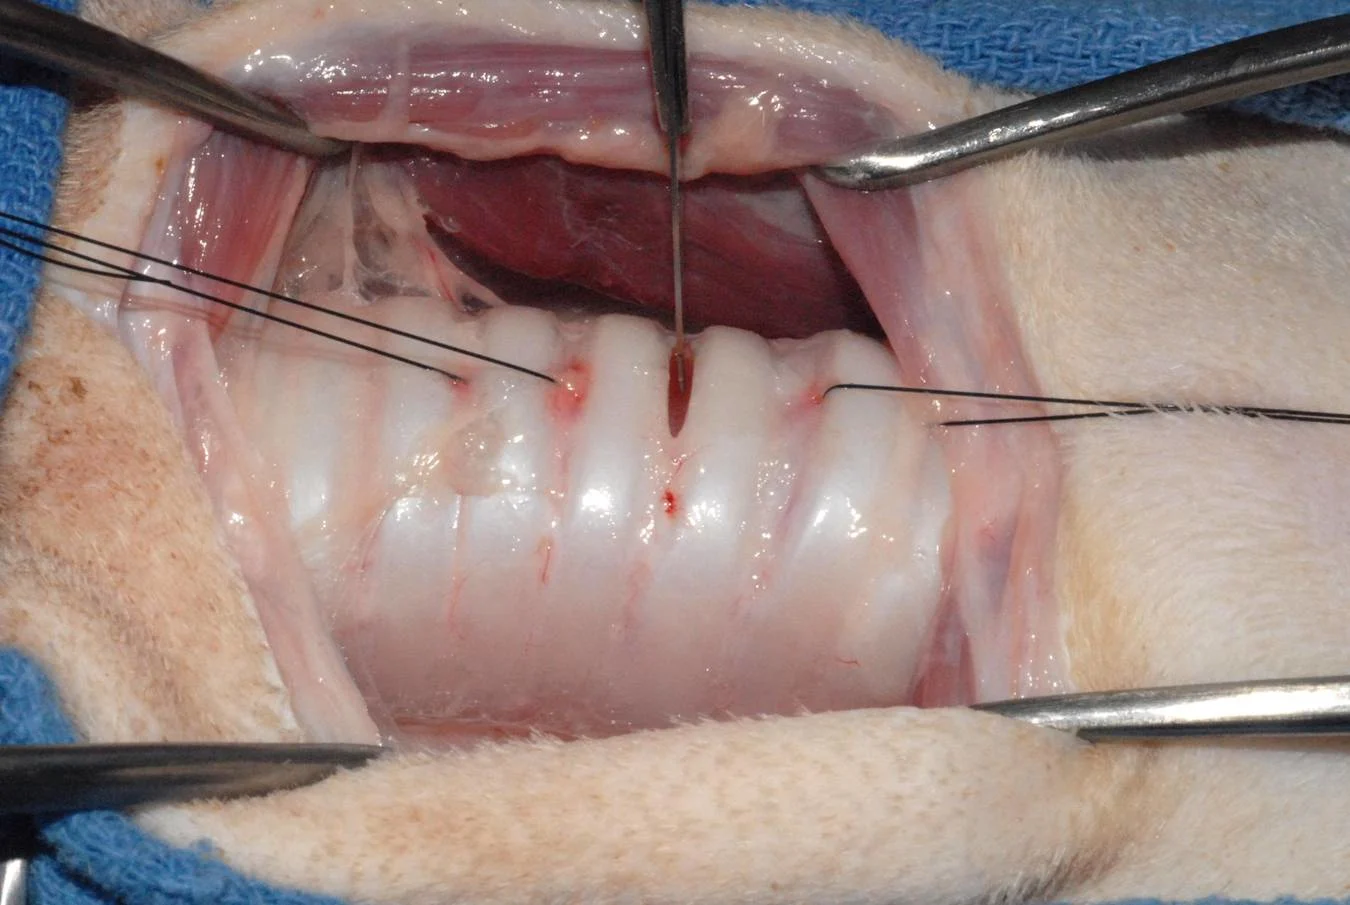

Step 8

When finishing the tracheostomy, I sometimes place 1 to 3 horizontal mattress sutures through the sternohyoid muscles (A and B). These sutures pass dorsally to the trachea and are tied to draw the sternohyoideus muscles dorsal to the trachea, elevating them toward the ventral surface of the neck. This reduces tension and minimizes the potential for soft tissues occluding the tracheostomy stoma. This step, although essential for a permanent trachestomy, is not required for every temporary tracheostomy.

Procedure Pearl

You can elevate the trachea toward the skin by drawing the sternohyoideus muscles dorsal to the trachea. This will minimize potential for soft tissue occlusion of the tracheostomy site.

A